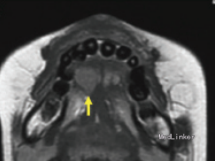

检查发现舌下有一隆起,约1.2*1cm大小,未影响舌功能和运动,唾液分泌正常,周围淋巴结无肿大。 影像检查显示右舌有一不规则圆形肿物,边界不清。

初步诊断为涎腺肿瘤,如多形性腺瘤。然而,由于患者被诊断为共济失调 - 毛细血管扩张症,考虑恶性淋巴瘤的可能性较大。全麻下手术切除,术后配合化疗。病理结果显示为弥漫性大B细胞淋巴瘤。